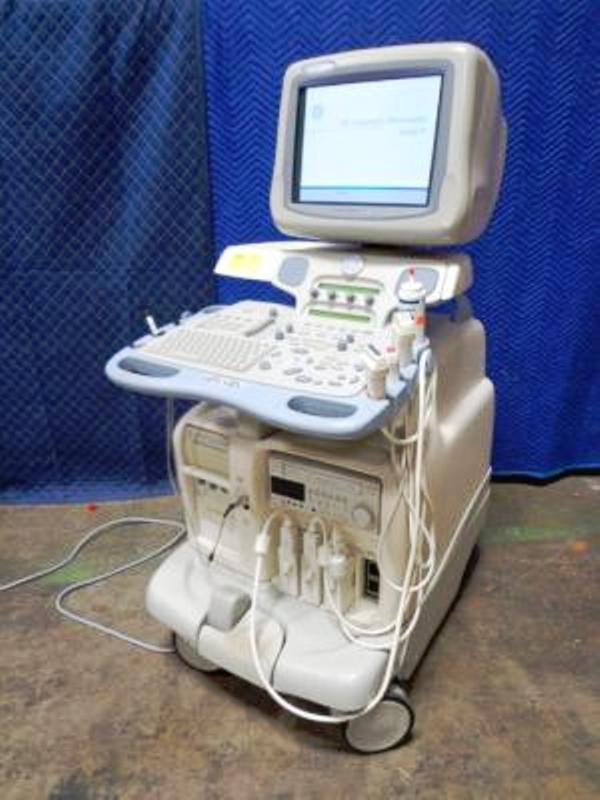

GE Vivid 7 Imaging Modes

GE Vivid 7 Features:

- 17" color CRT monitor

- 4 probe ports

- Floating keyboard with lifting swivel